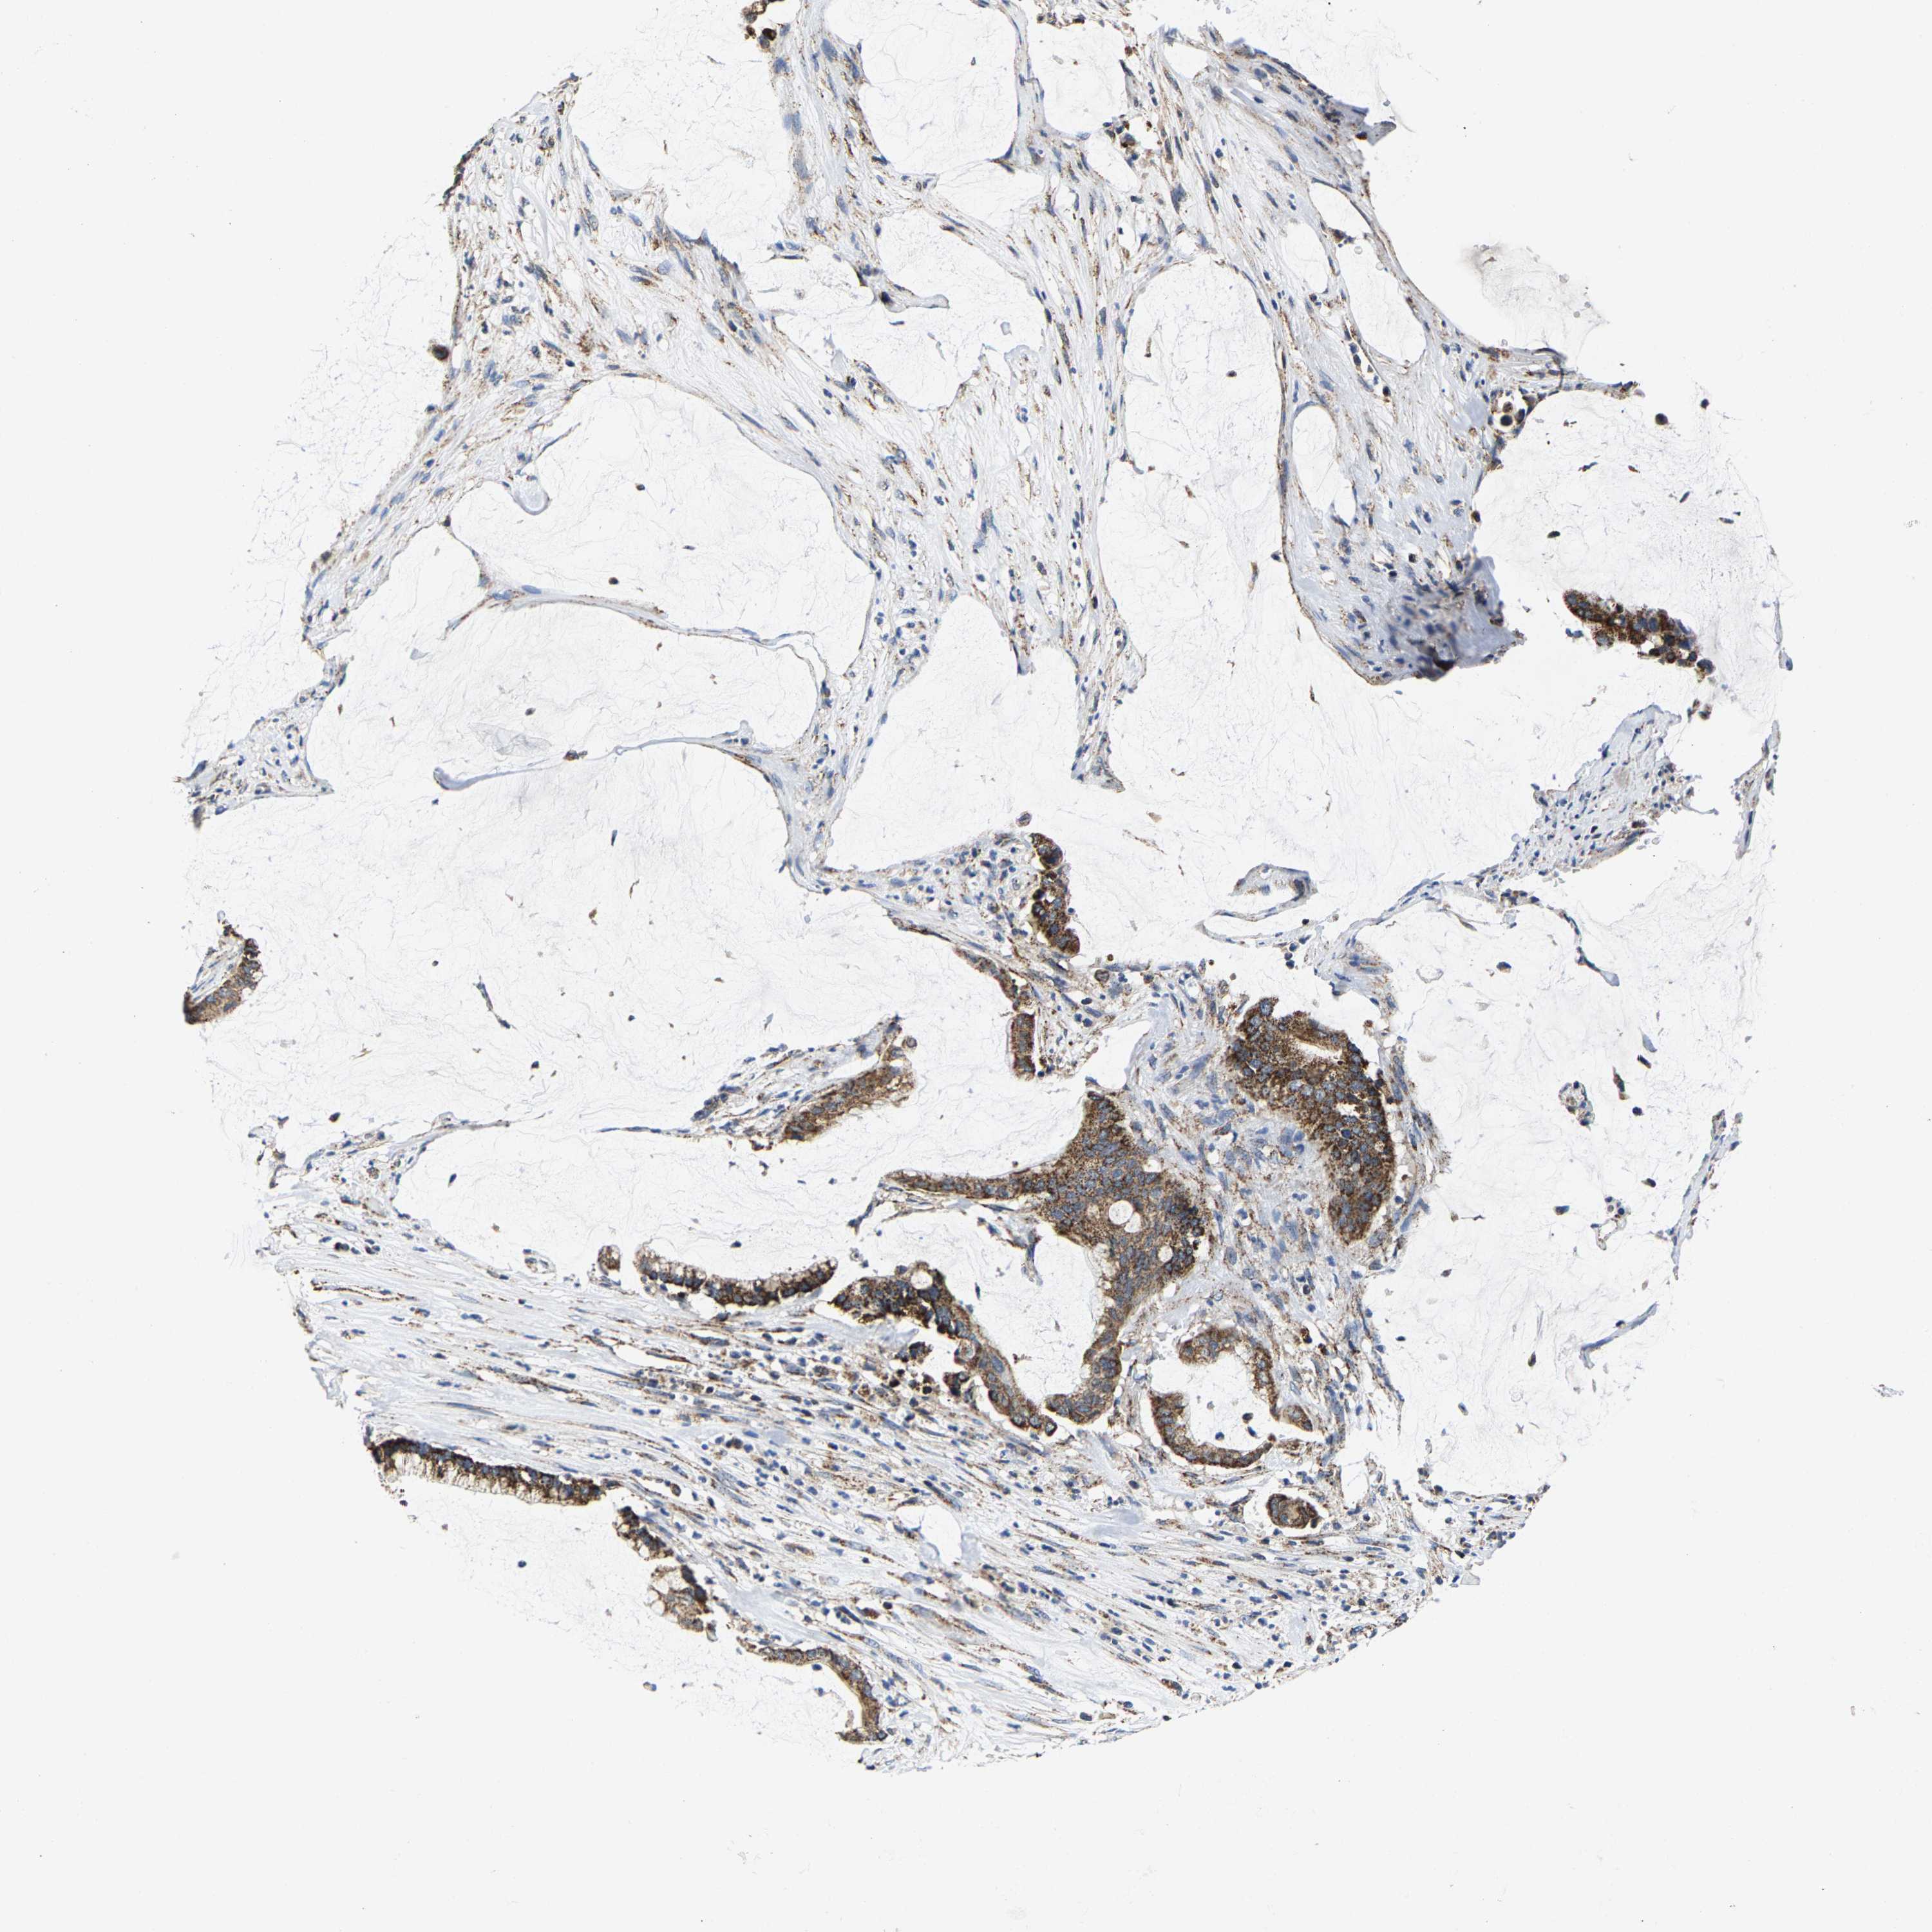

PANCREATIC CANCER - Protein expressioni

A mouse-over function shows sample information and annotation data. Click on an image to view it in a full screen mode. Samples can be filtered based on level of antibody staining by selecting one or several of the following categories: high, medium, low and not detected. The assay and annotation is described here.

Note that samples used for immunohistochemistry by the Human Protein Atlas do not correspond to samples in the TCGA dataset.

Antibody stainingi

Antibody staining in the annotated cell types in the current human tissue is reported as not detected, low, medium, or high, based on conventional immunohistochemistry profiling in selected tissues. This score is based on the combination of the staining intensity and fraction of stained cells.

Each image is clickable and will lead to virtual microscopy that enables deeper exploration of all samples and also displays staining intensity scores, fraction scores and subcellular localization as well as patient and tissue information for each sample.

Antibody HPA020543

Antibody HPA020549

Staining

High

Medium

Low

Not detected

Intensity

Strong

Moderate

Weak

Negative

Quantity

>75%

75%-25%

<25%

None

Location

Nuclear

Cytoplasmic/membranous

Cytoplasmic/membranous,nuclear

Adenocarcinoma, NOS